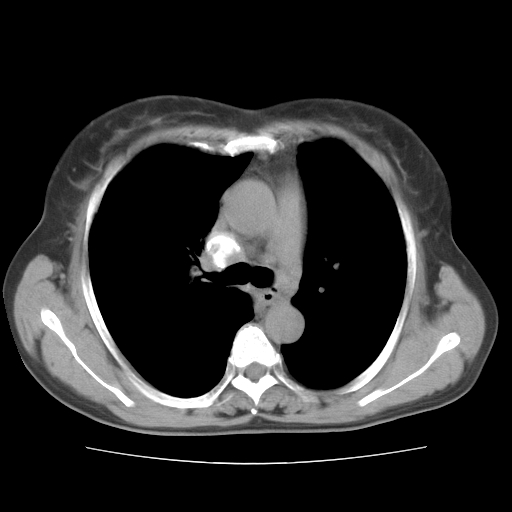

标题: CT10838:女性,56岁,是上腔静脉钙化还是淋巴结钙化? [打印本页]

标题: CT10838:女性,56岁,是上腔静脉钙化还是淋巴结钙化?

女性,56岁临床诊断为胃贲门ca,术前检查发现,此钙化灶,对此科内稍有争论!请各位老师看看!是上腔的还是淋巴结的?有意义吗?

淋巴结钙化可能性大,病灶较局限

淋巴结钙化,上腔静脉在外侧可看到.

胸锁关节层面的是淋巴结钙化,气管前腔静脉后的钙化灶占了4个层面,不知层厚是多少?看样子应该是7--10毫米之间,那么这病灶最小纵径得有28毫米!应该提示点什么了,没传肺窗,估计肺内没有病变?

考虑:上腔静脉后淋巴结钙化,没有什么意义。

左锁骨下静脉和头臂静脉会合后形成是上腔静脉,此钙化位于两血管回合的腔静脉后方、气管右前方,这个位置没有其他结构,应该是淋巴结钙化。一般多为淋巴结核后钙化,没有临床意义。